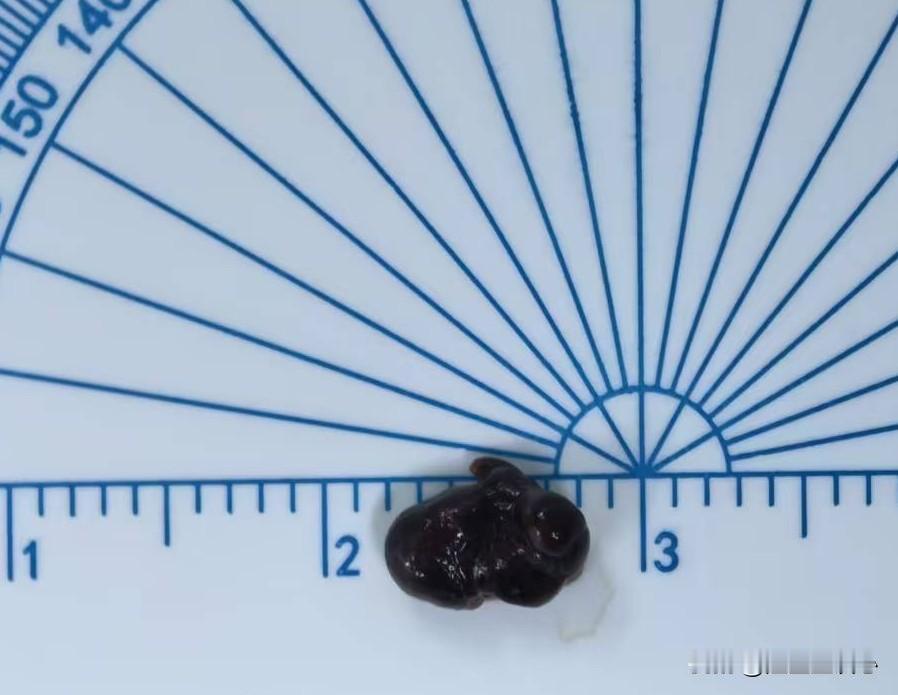

房颤患者突发肢体乏力要警惕脑卒中!昨天上夜班就碰到这样一例患者。这是一位49岁女性患者,因为风湿性心脏病心衰住院。住院以后用了抗凝药物预防脑梗,同时也用了一些心衰相关的药物。晚上9点钟左右,突然发现左手和左腿乏力,抬不起来。赶到床边看患者,发现左手的肌力大概在一级左右,右侧肢体肌力正常。这是很典型的急性脑梗的表现,立马让值班医生带患者去去急诊CT室做急诊的脑动脉CTA。 结果显示右侧大脑中动脉闭塞,这是心房颤动时,心房内的血栓随血液游走至大脑中动脉,无法通过,就堵塞了血管。紧急联系神经内科,做了急诊取栓手术,取出了一块血栓。 心房颤动(房颤)时心房没有了收缩功能,心房内血液容易淤积形成血栓,血栓随着血液流动到全身。引起一些脏器的栓塞症状。比如,栓塞了脑血管就会引起脑梗塞、偏瘫等症状。栓塞了肠系膜动脉,就会引起腹痛等症状。栓塞了脾动脉就会引起脾梗塞。所以房颤的治疗,最重要的就是预防脑梗塞等脏器栓塞并发症。方法就是口服抗凝药物,比如利伐沙班,艾多沙班,达比加群酯等等。 房颤治疗方法 房颤预防